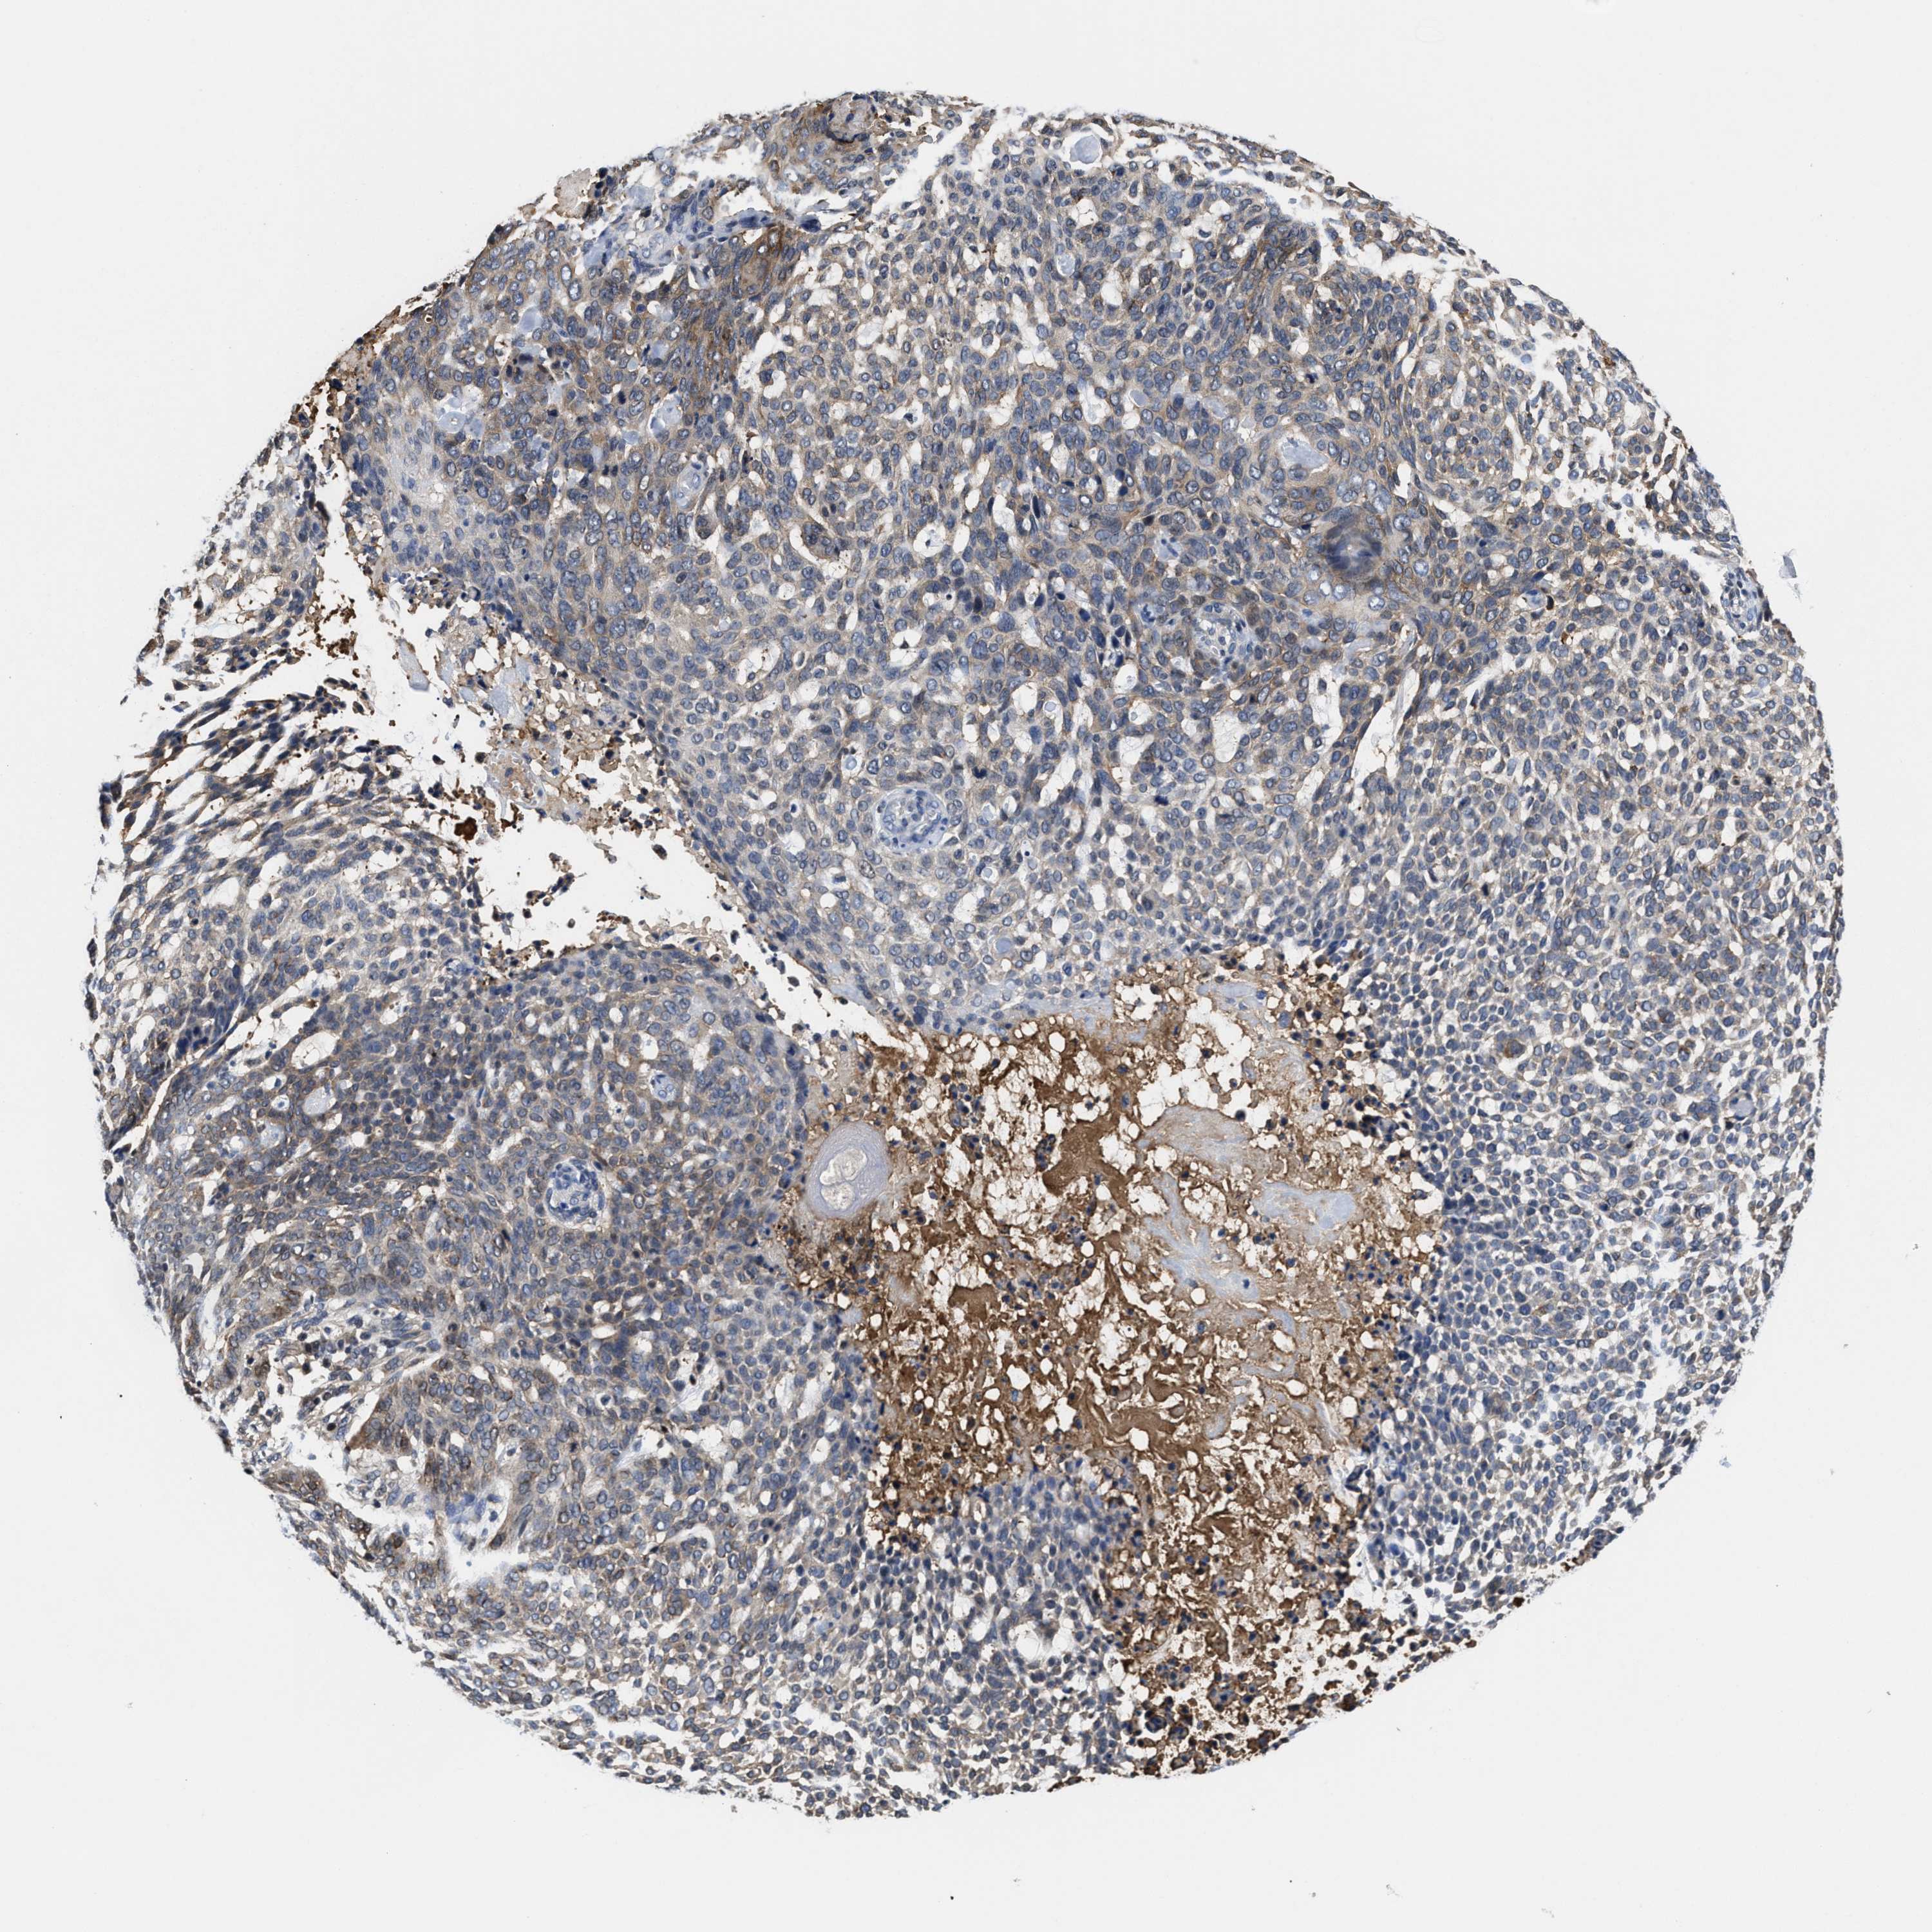

Basal cell and squamous cell cancer

SKIN CANCER - Protein expressioni

A mouse-over function shows sample information and annotation data. Click on an image to view it in a full screen mode. Samples can be filtered based on level of antibody staining by selecting one or several of the following categories: high, medium, low and not detected. The assay and annotation is described here.

Each image is clickable and will lead to virtual microscopy that enables deeper exploration of all samples and also displays staining intensity scores, fraction scores and subcellular localization as well as patient and tissue information for each sample.

Antibody HPA024127

Squamous cell carcinoma, metastatic, NOS